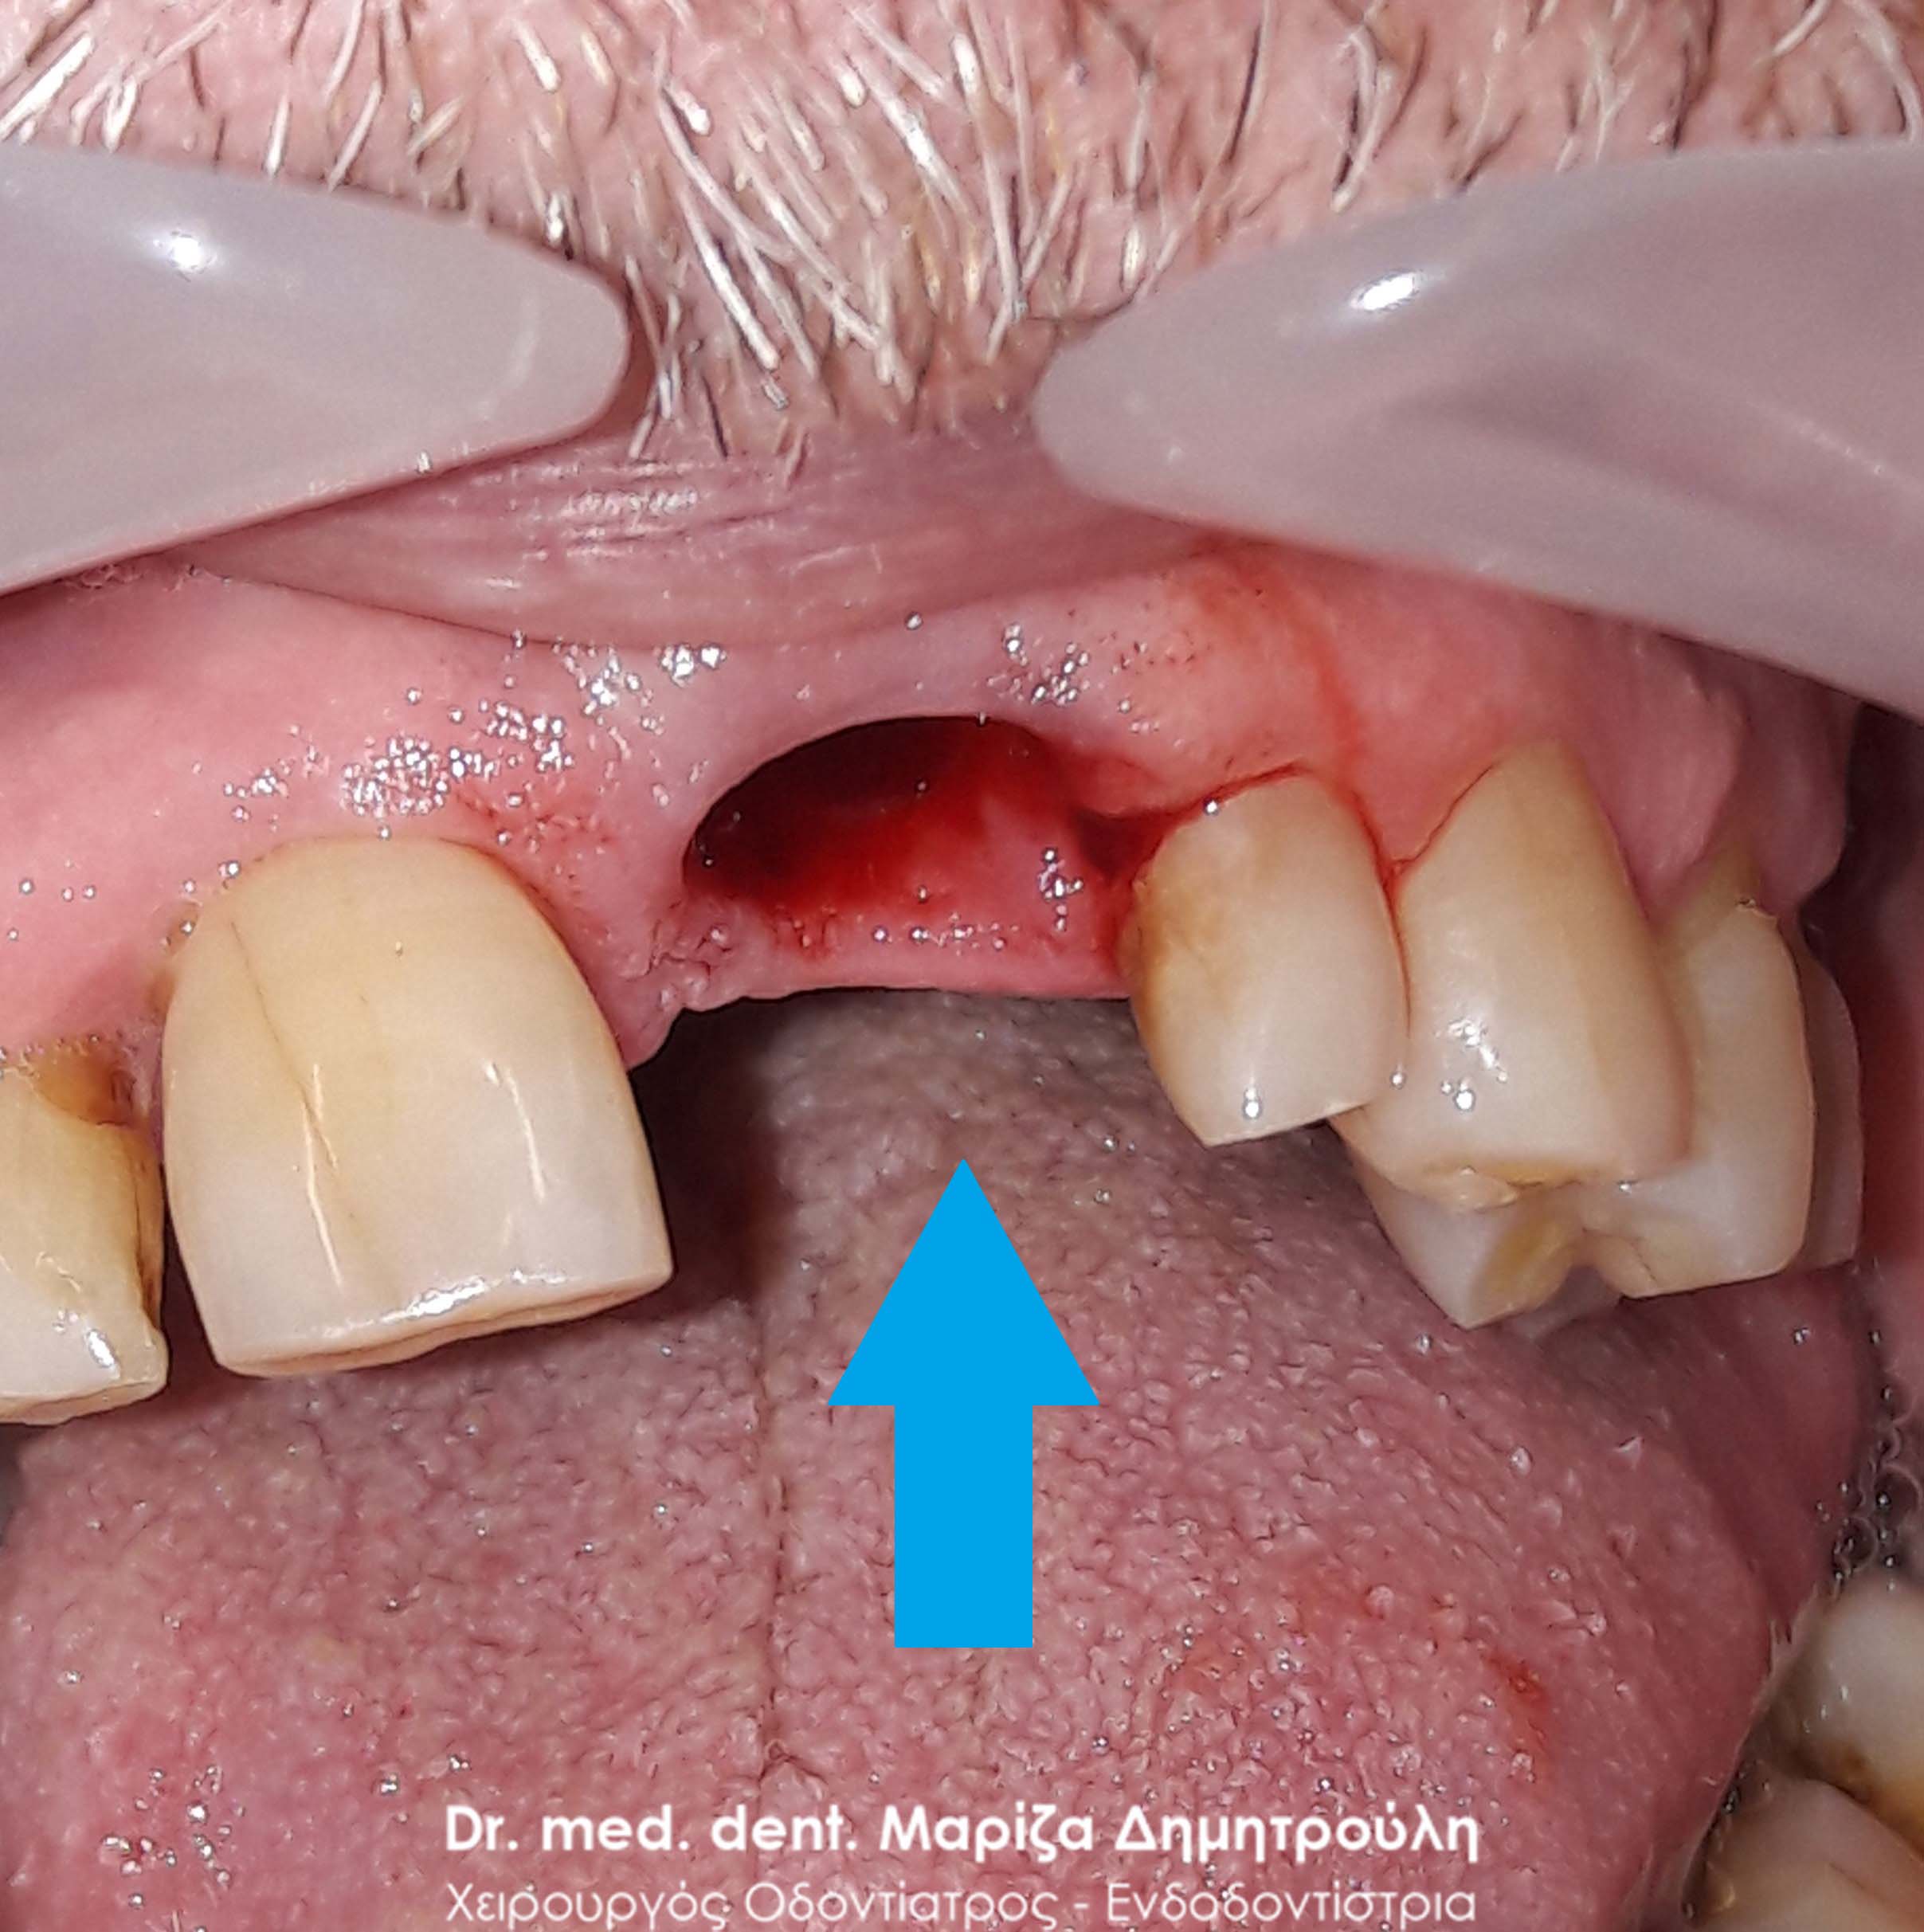

Ο ασθενής είχε για χρόνια μία πρόσθια νωδότητα στην κάτω γνάθο, την οποία αποφάσισε να αντικαταστήσει με προσθετική εργασία γιατί δεν αγαπούσε τα εμφυτεύματα. Μετά τις απαραίτητες εργασίες λήφθηκαν αποτυπώματα και κατασκευάστηκε ολοκεραμική γέφυρα, η οποία κάλυψε άριστα τόσο λειτουργικά όσο και αισθητικά το προϋπάρχον κενό.

Ο ασθενής είναι πολύ χαρούμενος με τα νέα του δόντια.

ΠΡΙΝ

ΜΕΤΑ